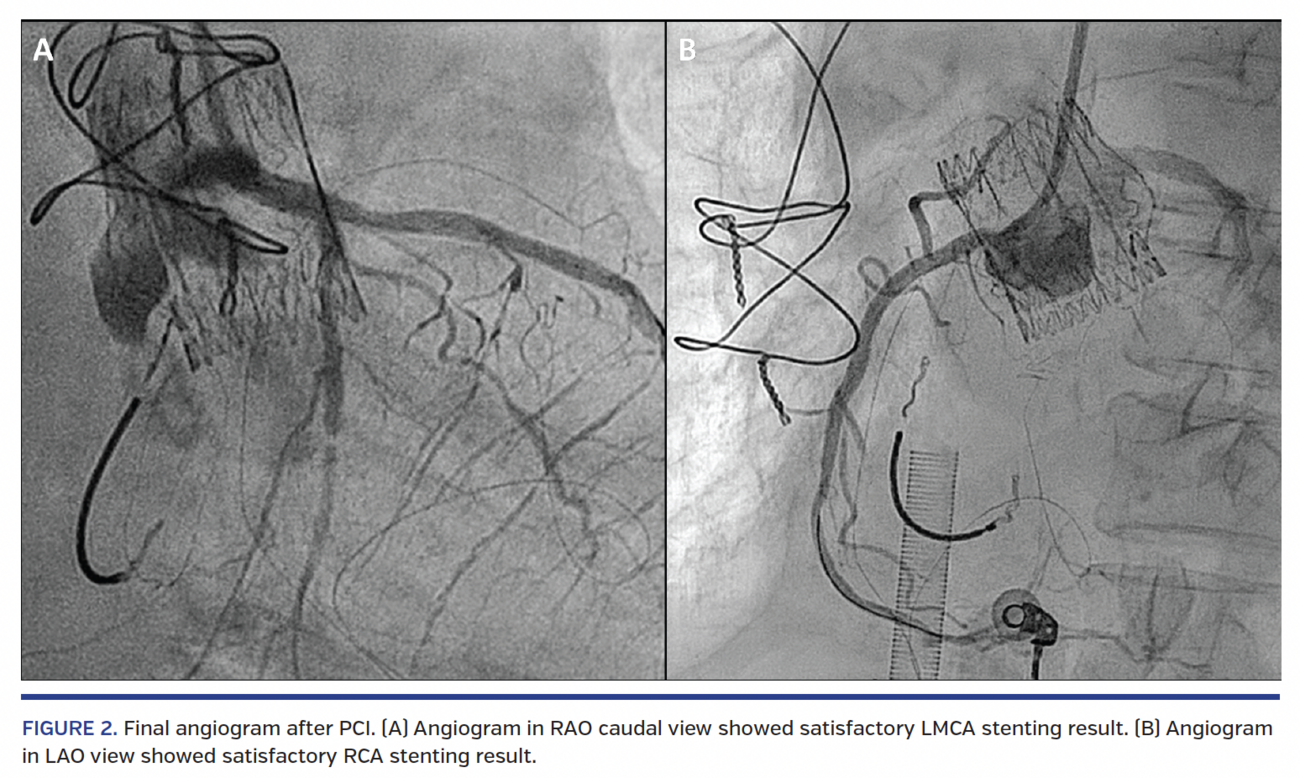

PCI was performed via right radial approach. The LMCA was engaged with difficulty due to distorted aortic root anatomy after Perceval valve implantation. It was eventually engaged through the stent cells with a 6 Fr Judkins left 3.5 guiding catheter (Cordis Corporation). Cross-sectional intravascular ultrasound of the LMCA (Figure 1) showed increased plaque load suggestive of accelerated atherosclerosis with evidence of prior coronary dissection. A 4.0 x 11 mm drug-eluting stent was used to cover the LMCA lesion with small protrusion beyond the ostium. In view of the blocked SVG, PCI to native RCA was performed in the same session with lesion preparation by rotational atherectomy. Final angiographic results were satisfactory (Figure 2). The patient was discharged 2 weeks later and remained free of chest pain.